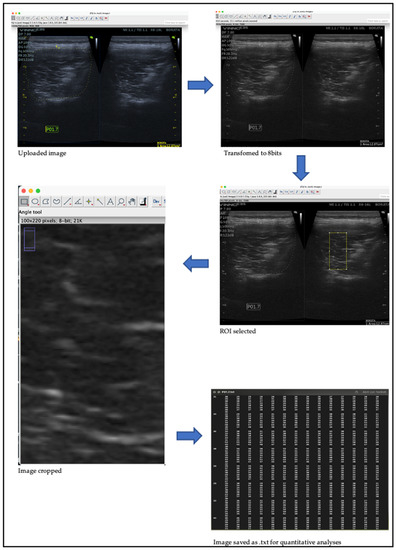

- Schindelin, J.; Arganda-Carreras, I.; Frise, E.; Kaynig, V.; Longair, M.; Pietzsch, T.; Preibisch, S.; Rueden, C.; Saalfeld, S.; Schmid, B.; et al. Fiji: An open-source platform for biological-image analysis. Nat. Methods 2012, 9, 676–682. [Google Scholar] [CrossRef]